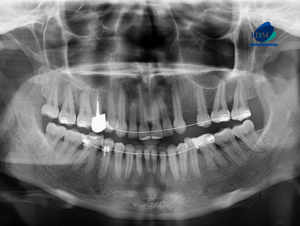

Paciente masculino de 37 años de edad acude al Instituto de Diagnóstico Maxilofacial con el motivo de consulta: descartar fractura radicular. Radiografia Panorámica A la